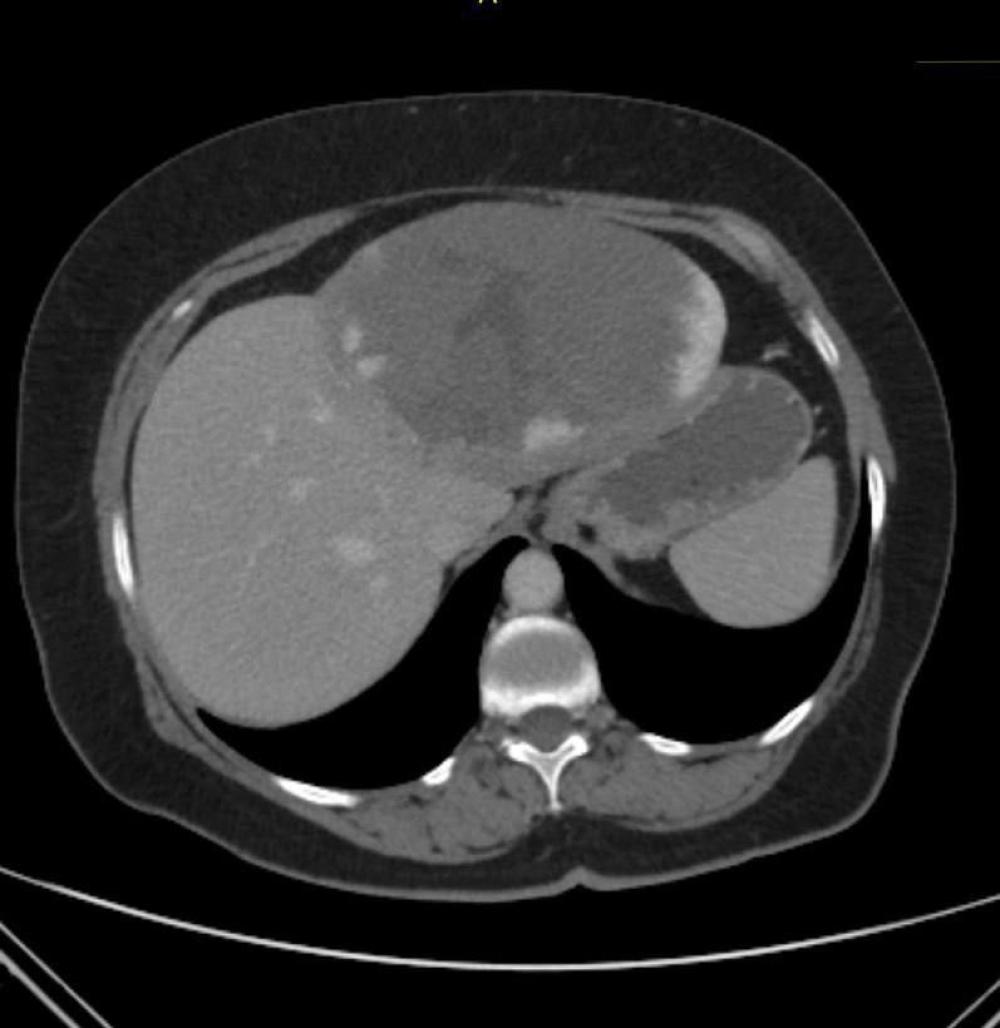

У Рівненському обласному протипухлинному центрі видалили 15-сантиметрову пухлину печінки.

Гемангіома печінки – найпоширеніша доброякісна пухлина печінки, її виявляють у 2–20% населення. У більшості випадків немає симптомів і лікувати нічого не треба.

Відомо, що пацієнтці 64 роки, вона лікувалась у протипухлинному центрі кілька років тому і тепер раз на рік проходить КТ в межах Follow-up. В динаміці гемангіома її печінки збільшилась від 4 до 15 сантиметрів за рік.